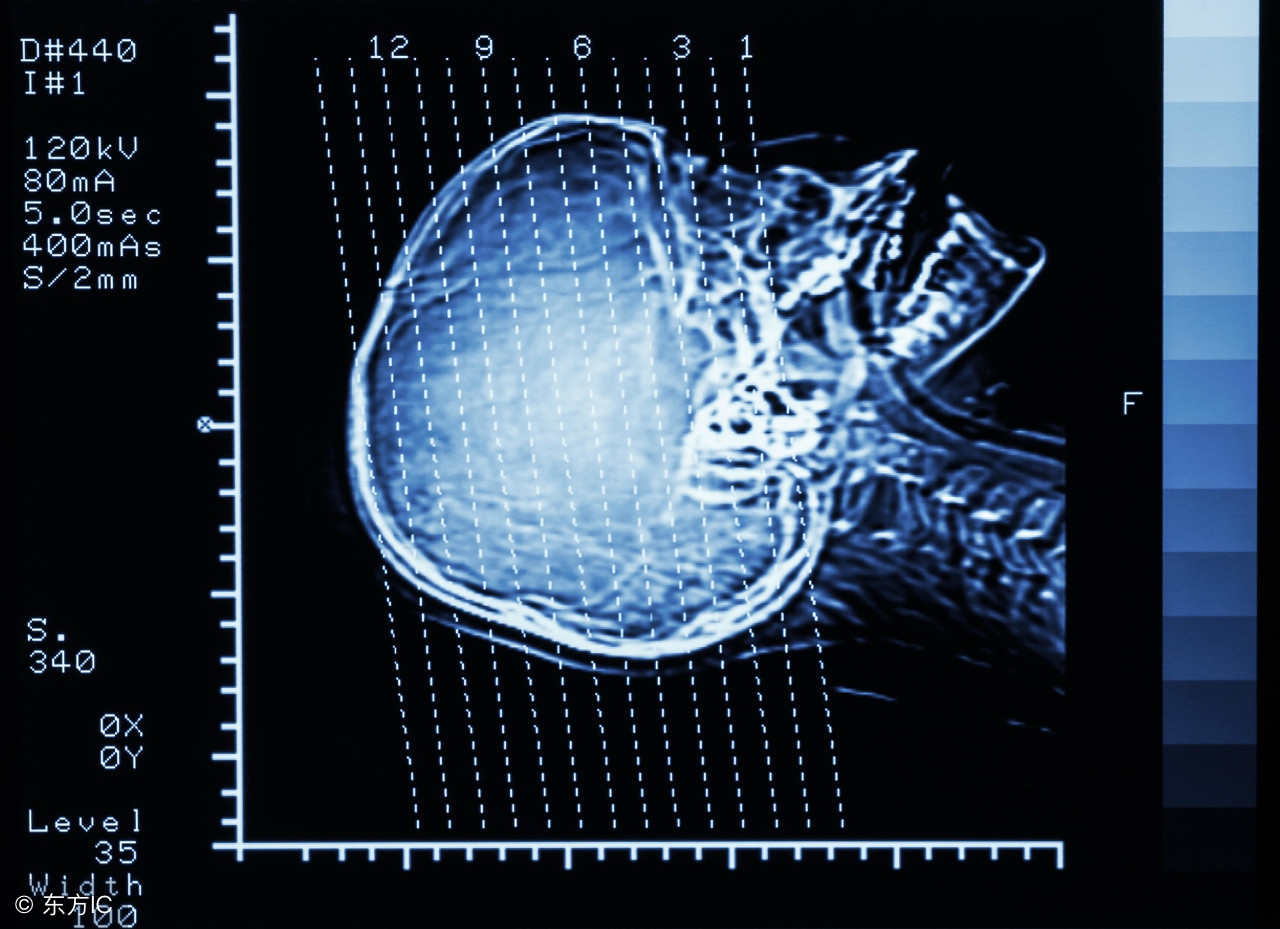

3、检查——明确梗死部位!

CT、MRI、TCD、血管影像(CTA、颈动脉超声、超声心动图)。